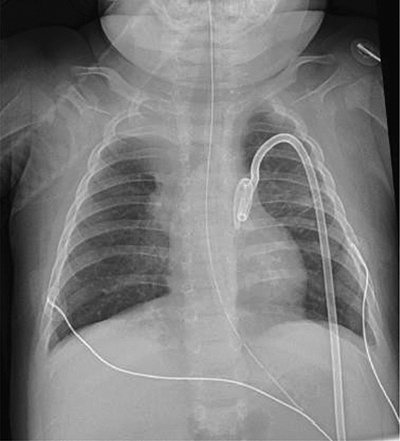

Mechanical ventilation was performed to improve the patients episodes of apneas and desaturation but resulted shortly after in free air located at the infra-thoracic part of the chest radiograph (Figure 3A and B), treated by the placement of two left thoracic drains.

Figure 3

(A, B) Chest and abdominal antero-posterior radiograph.

Free air (subcutaneous emphysema) located at the infra-thoracic part of the chest radiograph.